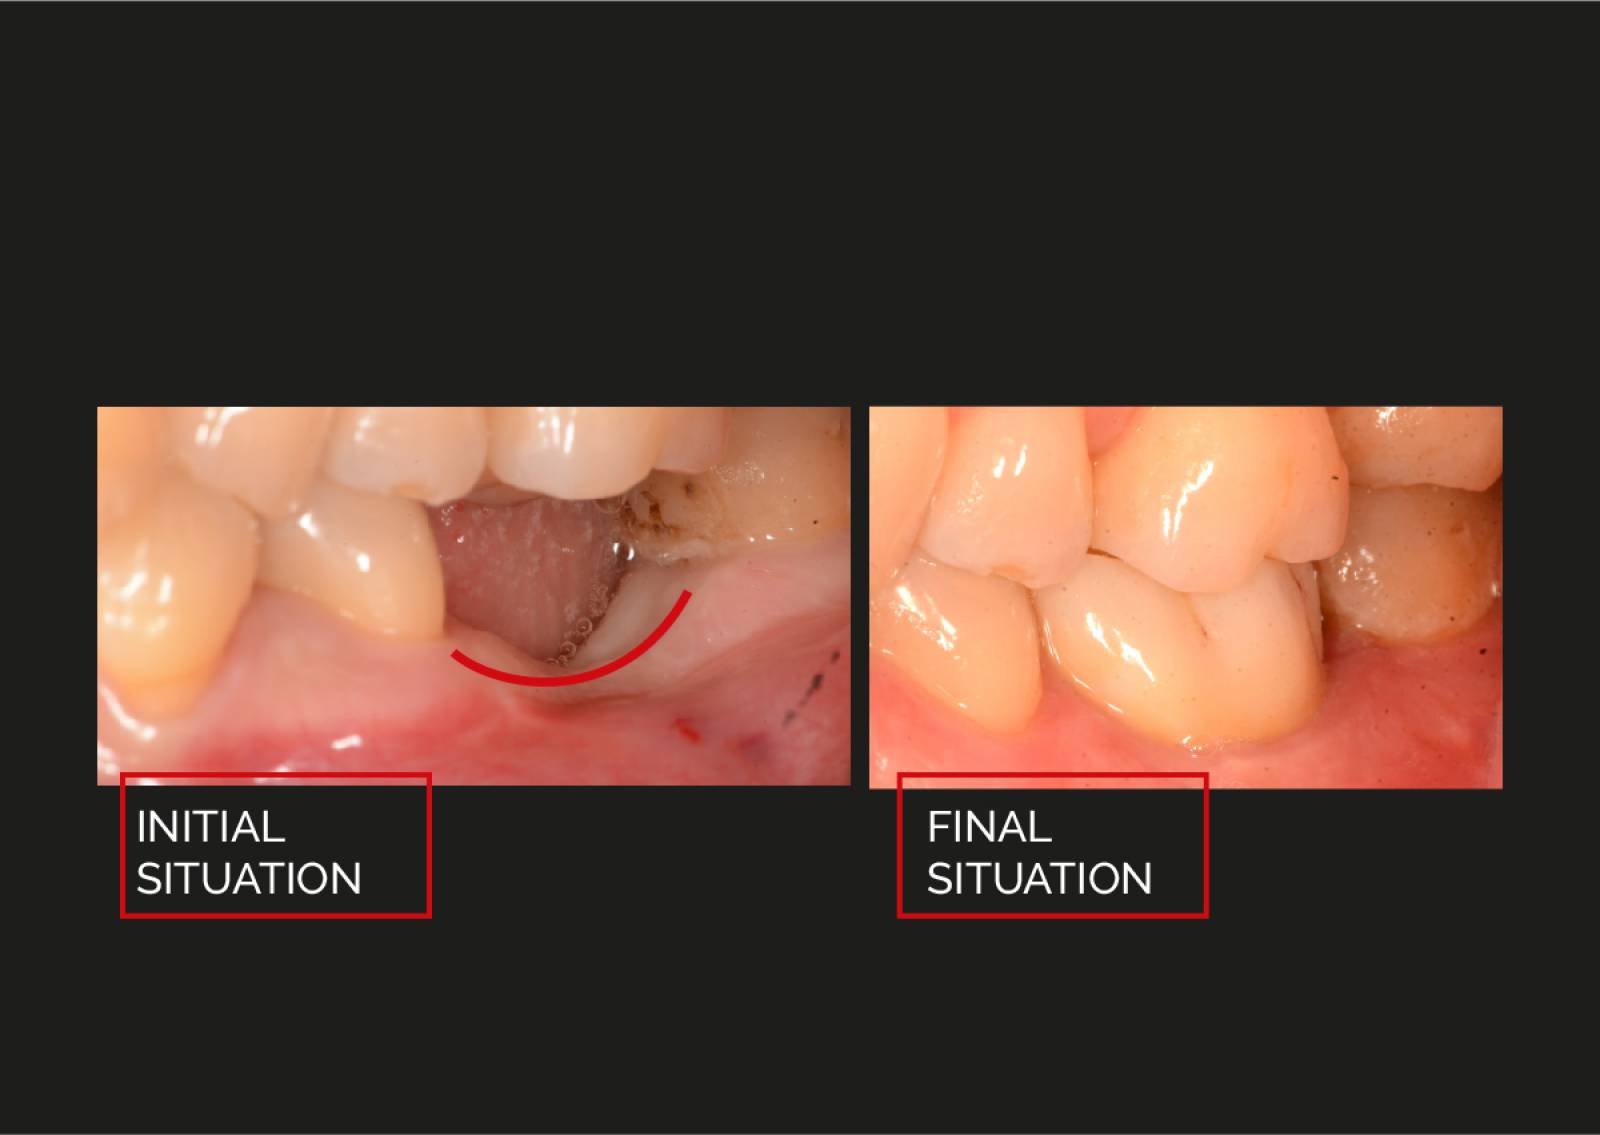

PROSTHETIC

Handling of the matrix® prosthetics.

The precision of matrix® prosthetics.